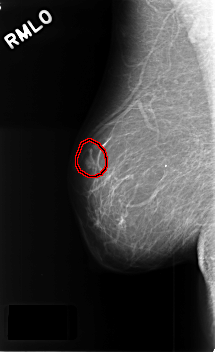

C_0382_1.RIGHT_MLO

RIGHT_MLO LINES 4576 PIXELS_PER_LINE 2784 BITS_PER_PIXEL 12 RESOLUTION 50 OVERLAY

FILE: C_0382_1.RIGHT_MLO.OVERLAY

TOTAL_ABNORMALITIES 1

ABNORMALITY 1

LESION_TYPE MASS SHAPE OVAL MARGINS CIRCUMSCRIBED

ASSESSMENT 3

SUBTLETY 5

PATHOLOGY BENIGN

TOTAL_OUTLINES 1

BOUNDARY